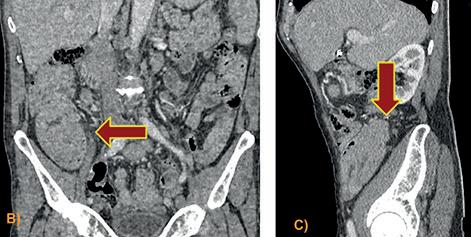

FIGURA 2. Tomografía de abdomen y pelvis con contraste EV: Se evidencia invaginacion intestinal (Signo de donut o escarapela) en asa correspondiente al yeyuno proximal, en cuya porción distal impresiona existir una lesión de contornos lobulados con refuerzo considerable post-contraste que podría corresponder a la cabeza de la misma y estar en relación a un pólipo pediculado. Mide 3 cm. en su diámetro mayor. No se observa una ostensible dilatación de la luz proximal. Los planos grasos mesentéricos tienen aspecto conservado A)- B)-C).Signo de la salchicha o pseudoriñón. Servicio de Tomografía, Departamento de Imágenes, Hospital de Clínicas “Jose de San Martin” [Av. Córdoba 2351, CABA].

(12/21) con posterior colocación de stent y múltiples episodios de hemorragia digestiva alta posteriores, que requirió internación (2022) por shock hemorrágico. Se realiza tomografía con de abdomen y pelvis con contraste endovenoso donde se constata intususcepción intestinal de porción proximal de yeyuno. (Figura 2)